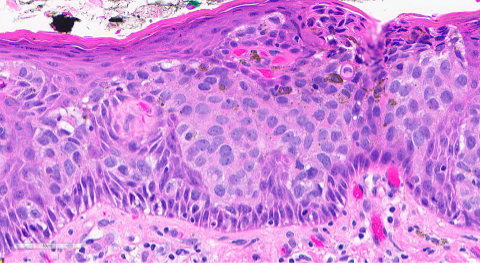

Figure 2. Section from the right vulva. The epidermis is composed of nests of tumor cells with large, vesicular nuclei with prominent nucleoli and abundant pale, eosinophilic cytoplasm. There are also intracytoplasmic vacuoles and dark pigment.

Primary Paget disease of the vulva is a rare in situ adenocarcinoma that arises in the labium minus or majus and most commonly affects postmenopausal women. Patients may present with itching or burning that has been present for years before undergoing a biopsy. On physical examination, the vulvar lesion is raised and may look erythematous or eczematous and can extend to the vagina and cervix. On microscopy, the tumor cells may be singly dispersed or arranged in a nested pattern. The nuclei are large and vesicular with prominent nucleoli. There is abundant pale, eosinophilic cytoplasm and intracytoplasmic mucin can be seen. The tumor is most commonly positive for CK7, GATA3, CEA, and GCDFP-15 and negative for PAX8, SOX10, and HPV ISH. This panel is helpful when differentiating it from other entities. However, there are reports of p16 and PAX8 positivity in Paget disease of the vulva, so careful interpretation of morphologic features and ancillary studies is important.

In some cases, there may be melanin pigment throughout the epidermis and dermis, which gives rise to a melanoma differential. In this situation, SOX10 and Melan-A will stain the background melanocytes; however, the Paget tumor cells will be negative. Other differentials include vulvar intraepithelial neoplasia, HPV-independent (dVIN), high-grade squamous intraepithelial lesion (HSIL) with pagetoid spread, and secondary Paget disease. dVIN can microscopically look like Paget with the nested, pale tumor cells, as well as mucinous differentiation, however, it will be negative for CK7 and GCDFP-15. HSIL can mimic Paget with mucinous areas, melanin pigment, and pagetoid spread too. To best differentiate HSIL from Paget, high-risk HPV ISH is useful, as it will be positive in HSIL and negative in Paget. The last differential is secondary Paget, which is much less common and originates in another location before metastasizing, such as the rectum, cervix, or bladder. These would stain for CDX2, CK20, or uroplakin-3, respectively.